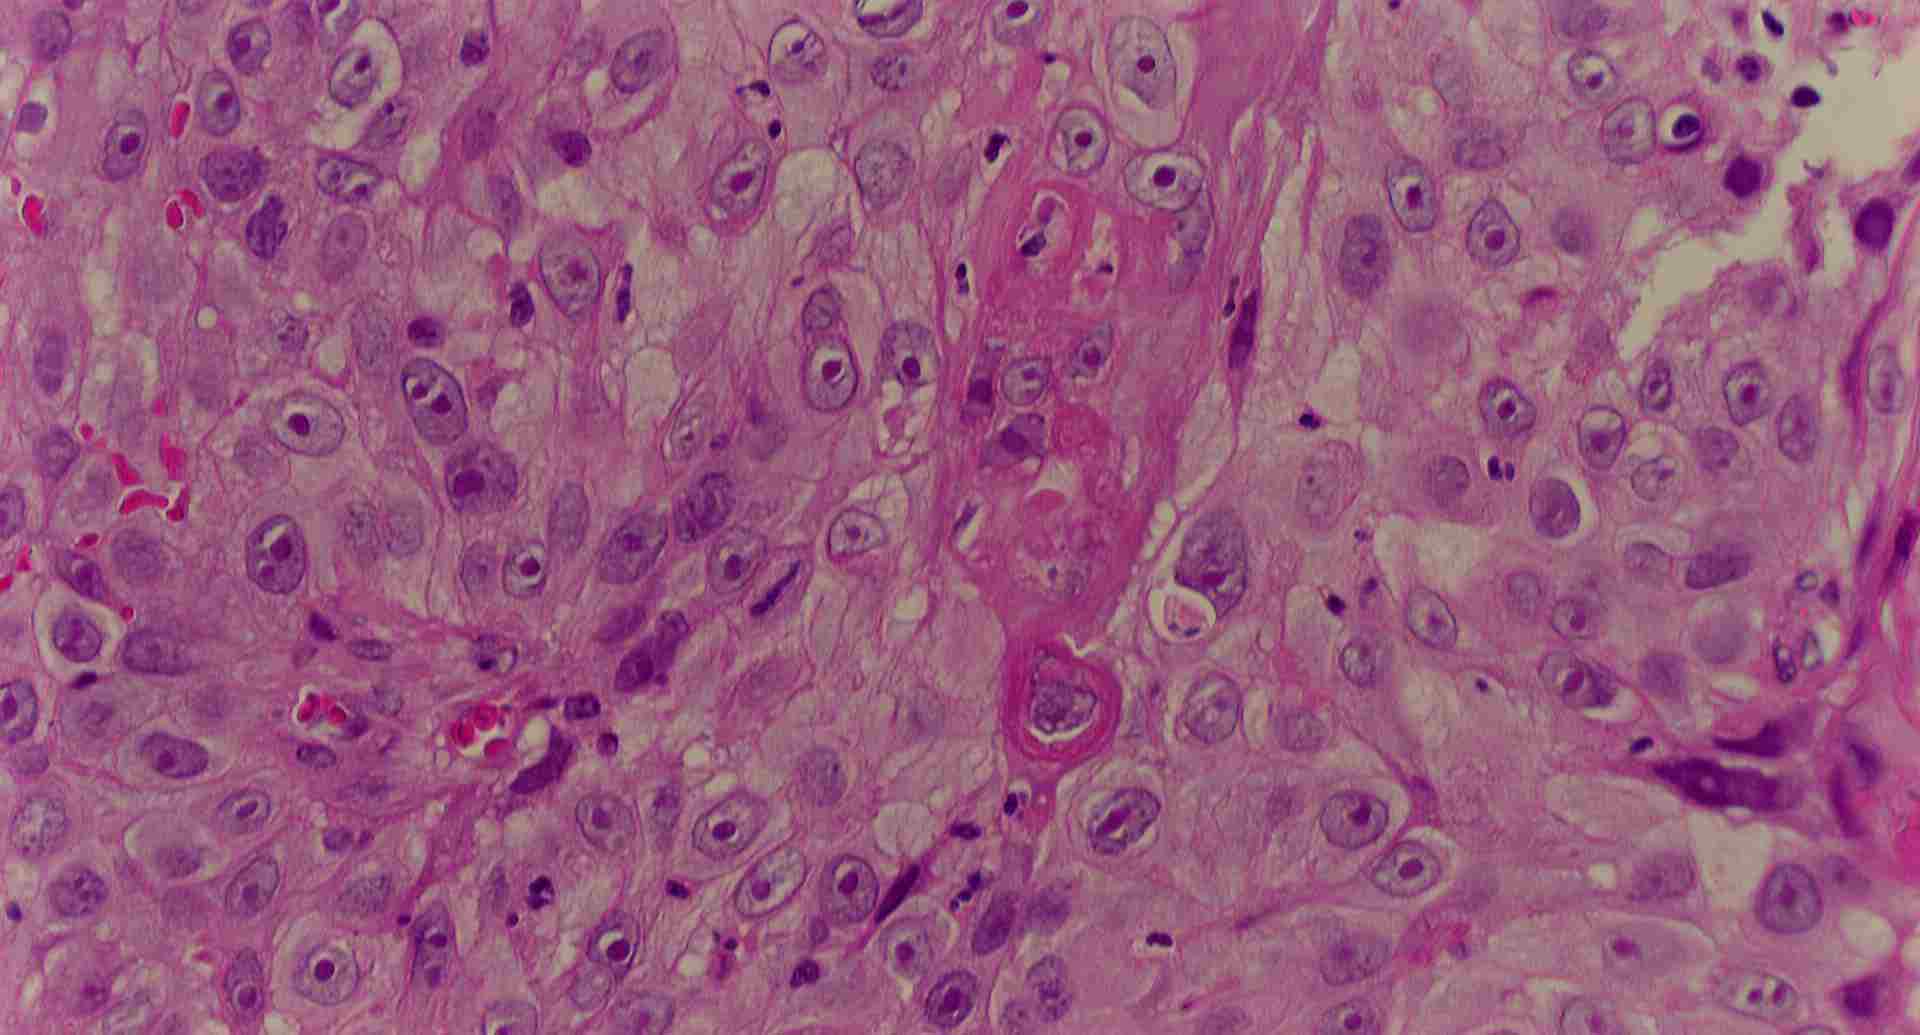

標本10

標本10の説明